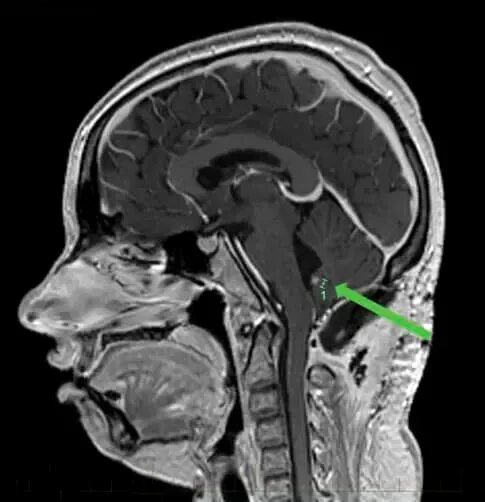

Бластома мозга